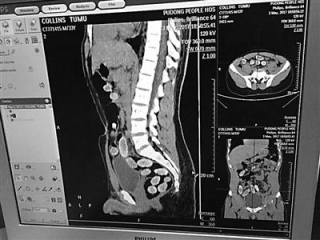

上海浦东国际机场海关查获一起人体藏匿走私毒品案件,缴获海洛因净重389.68克 海关供图

5月3日,上海浦东国际机场海关关员在对一批搭乘航班自非洲入境的旅客例行查验时,发现一名外籍男子神情异常。在对这名旅客进行人体X光机检查时,图像显示,其腹内存有异物,疑似人体藏毒。